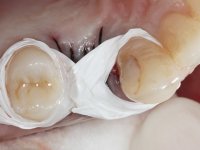

A CT scan was performed to evaluate the available bone heritage and to choose the type and size of implant to be placed. An impression of both jaws was made in alginate, as well as intermaxillary recording for laboratory work on a provisional prosthesis. The provisional prosthesis was made by including a metal wire in a prosthetic tooth adapted to the edentulous space. The root was carefully removed and the implant was placed in the tooth socket corresponding to tooth 1.4. The remaining space between the walls of the alveolus and the implant was filled with regenerative material and then sutured. The prosthesis was previously adapted to the postoperative zone and was then bonded to adjacent teeth. Teflon was used to promote the best possible insulation. Bonding was done using photopolymerizable composite resin using the palatine and inter-proximal walls of the adjacent teeth. After 10 days, the suture was removed and one month later osseointegration was confirmed. Exposure of the implant and placement of the healing screw was performed after 10 weeks. The cervical portion of the provisional tooth had to be reduced to accommodate the healing screw. Stabilized peri-implant soft tissues were impressed using open tray technique with soft and regular consistency putty silicon. In the laboratory the work model was made, along with the choice of pre-fabricated components for the confection of a metal-ceramic crown screwed to the implant with the brand’s interface. Removal of the provisional bridge was done with great care not to touch the interproximal surfaces of the teeth adjacent to the edentulous space. The crown was screwed to the implant, and after imaging, the seating was given the final tightening with 35N of torque. The screw access hole was filled with Teflon and closed with composite resin. The patient manifested satisfaction with the aesthetic and functional rehabilitation achieved.